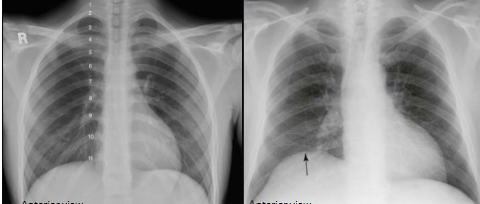

Paradoxical breathing

abnormal breathing pattern where the chest contracts while abdomen rises during inhalation

happens due to injured phrenic nerve

elevation of the diaphragm on the affected side